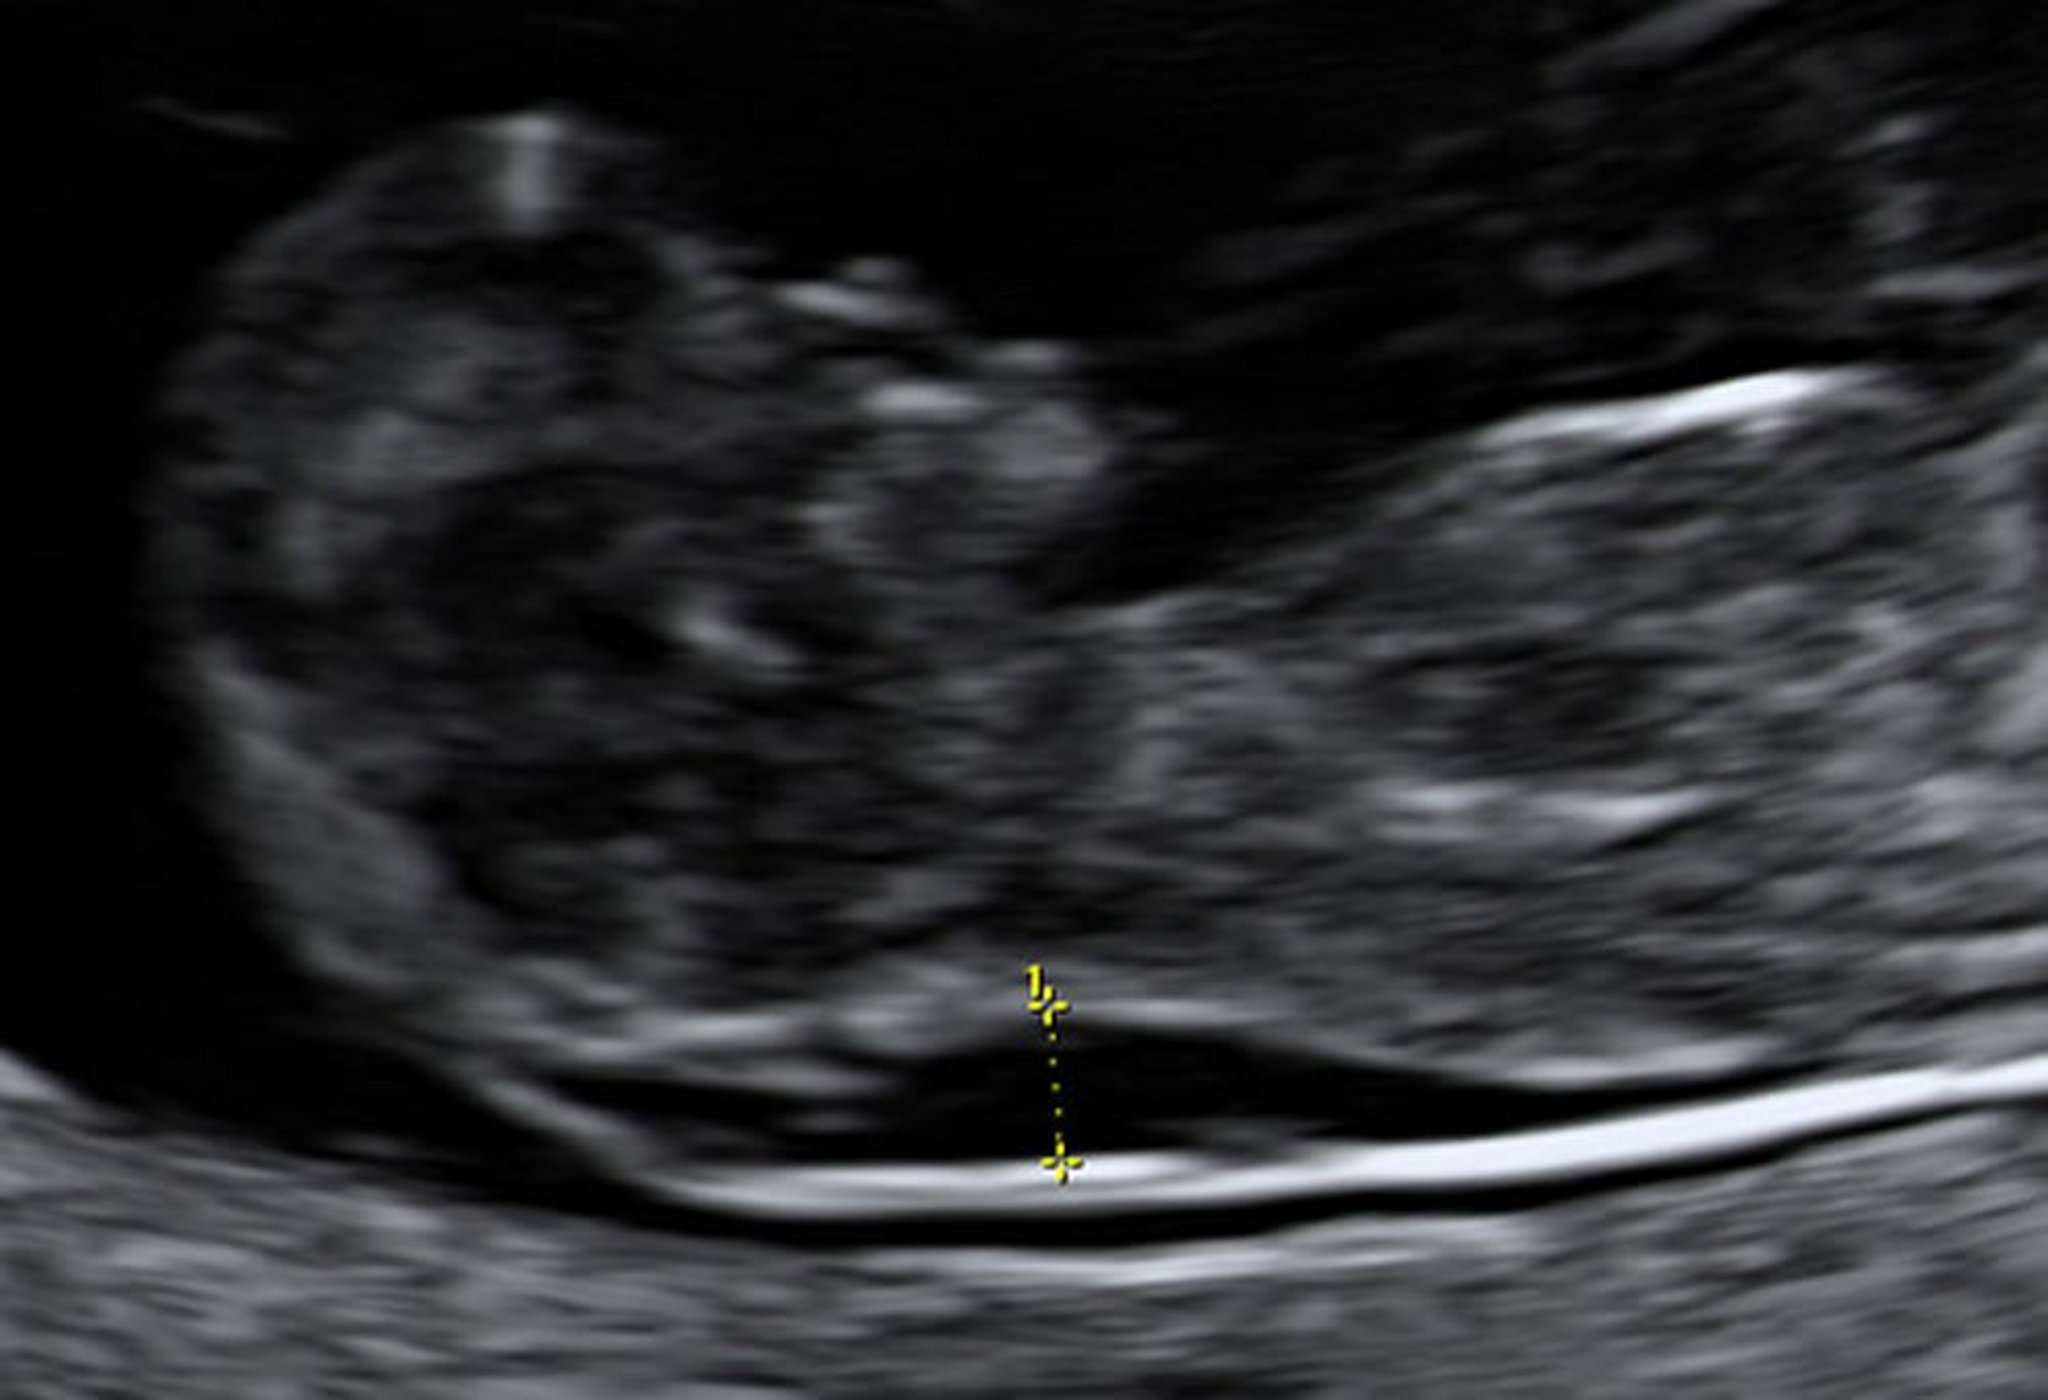

Ecografía que muestra aumento de la translucencia nucal en un feto a las 10 semanas

La biopsia de vellosidades coriónicas indicó que este feto tenía síndrome de Down.

Foto de Jeffrey S. Dungan, MD.